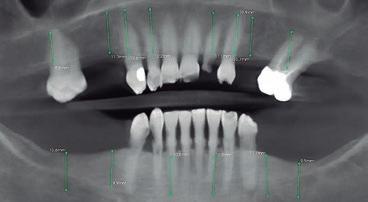

Paciente de 59 años acude a consulta en búsqueda de un tratamiento fijo sobre implantes con la finalidad de restituir la función y estética de forma inmediata. Durante la exploración intraoral se observan numerosas ausencias de piezas dentales, lesiones cariosas en los dientes restantes y una enfermedad periodontal generalizada como agente causal de la gran pérdida ósea y la consiguiente movilidad dental de los FIG. 1. Situación inicial,vista extraoral. dientes presentes en boca (figs. 1 y2). El examen clínico se complementa con una tomografía computarizada de haz cónico (CBCT). Se propone un plan de tratamiento (fig. 3) que abarca los siguientes pasos: Q En el maxilar: extracciones de las piezas: 11, 12, 13, 17, 21, 22, 23, 26 e implantes en posición 11, 12, 13, 16, 21, 22, 23, 26. Q En la mandíbula: extracciones de las piezas 31, 32, 33, 42, 44, 46 e implantes en posición 32, 34, 36, 42, 44, 46. Q Restauración provisional fijo en ambas arcadas de carga inmediata con electrosoldadura intraoral. La intervención quirúrgica se realiza bajo sedación consciente intravenosa. El médico anestesiólogo, previo a la cirugía, administra los fármacos necesarios según las necesidades y requerimientos del paciente. A lo largo de la cirugía y en todo momento, el paciente se encuentra monitorizado a través del uso de un pulsioxímetro. Se inicia el

FIG. 3. Diagnóstico CBCT. FIG. 4. Incisión y despegamiento.